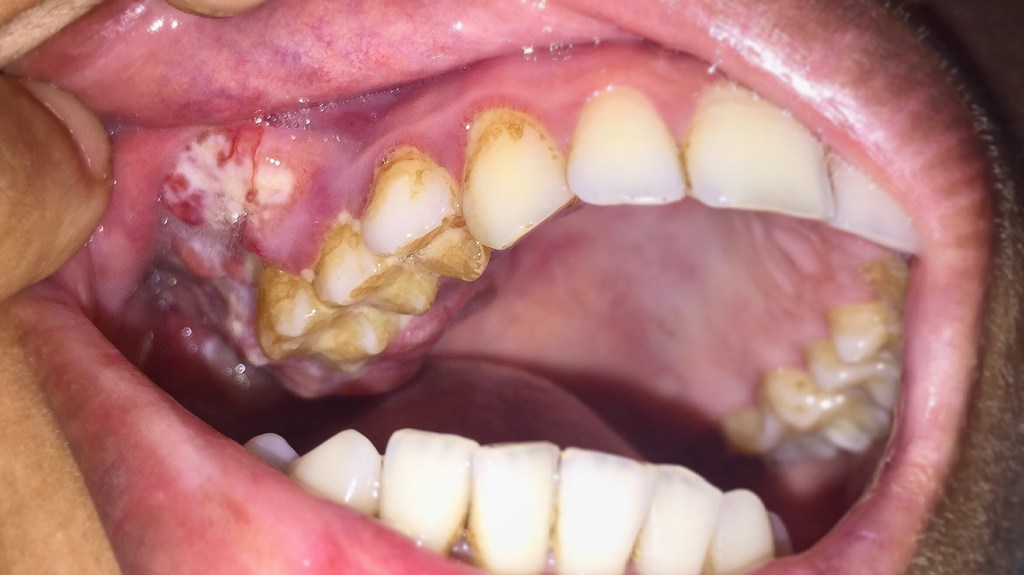

Gum Cancer Signs

There are certain signs that come about with gum cancer specifically. Patches or growths which are irregular are signs of this. They may be swollen and white in terms of color. They’re called scientifically erythroleukoplakia (white and red patches or growths) and also ones that are only white and only red. The ones that are just whit usually appear to be benign, but anything that’s red, or a combination of the two is something to be mindful of.

Gum cancer is different from gum disease, and the problem is that it does spread in a quick manner, so early detection is something which offers the best outcome. If you notice growths within your gums that haven’t been cleared in at least a couple weeks, you might want to get a biopsy.